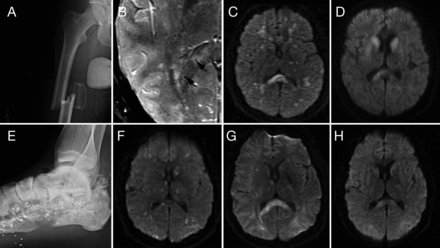

21岁以前健康的人也有权利关闭midshaft股骨髌骨骨折和机动车事故(图,一个)。四个小时后,他接受了右膝灌溉和清创术,后跟一个近端胫骨牵引销位置。十个小时后,这个过程中,他成为了困惑,不安,血氧过低的(血氧饱和度60%),降血压药(血压86/58毫米汞柱),和tachycardic(140脉冲/分钟)。他现在昏迷,自发的伸肌反应。皮肤瘀点。胸部CT显示双边肺水肿。经胸廓的超声心动图(TTE)显示dyssynchronous室间隔和右心室收缩压升高与急性肺动脉高压一致。好几天了,他仍然昏迷和发达的发热、心动过速,大汗。他被诊断出患有PSH并得到了普萘洛尔,加巴喷丁和可乐定。为了更好的控制这些事件,氯羟去甲安定,芬太尼和吗啡也管理。 Brain MRI on day 5 showed multiple diffuse hypointense foci on susceptibility-weighted sequence (SWI) and innumerable foci of reduced diffusion in a “starfield” pattern, compatible with fat embolism (图中,B和C)。

上一行(案例1):右腿的x光照片显示关闭midshaft股骨骨折(一个);第五天,轴向susceptibility-weighted成像序列显示多个点状的疫源地hypointense信号在整个大脑(黑色箭头标志)(B);多焦点的限制扩散模式(星际)diffusion-weighted成像序列(驾车)(C)和23天随访MRI显示分辨率的一些病变驾车序列(D)。较低的行(例2):x光照片的左脚和跟骨显示无数微小的金属碎片在软组织和骨骼和多个跟骨骨折与软组织肿胀(E);第一天首先MRI显示多个领域的限制扩散在酒后驾驶星际序列特征模式(F);7天随访MRI显示的微小病变进展汇合的模式(G);在30天随访MRI显示明显细胞毒性水肿(H)的决议。

他在2周开始睁开眼睛,最终做出了一个惊人的复苏。在随访MRI有点状的进化限制扩散尾汇合的信号变化和胼胝体压部(图D)。Neuropsychometric测试显示,认知速度和执行功能障碍。在12个月的随访,他可以兼职工作。